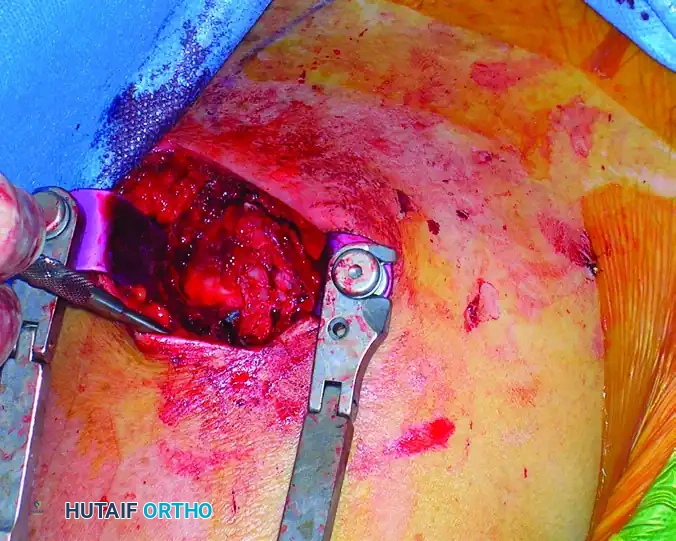

Rotator Cuff Management

Once the subdeltoid bursa is excised, the rotator cuff footprint is visualized. Under direct observation, incise the supraspinatus tendon in line with its fibers (longitudinally) to access the articular surface of the humeral head.

Place heavy, full-thickness non-absorbable stay sutures (e.g., #2 FiberWire or similar) into the anterior and posterior leaflets of the incised rotator cuff. These sutures serve a dual purpose: they act as retractors to expose the entry point and, crucially, they protect the cuff tissue from being macerated by the reamers during canal preparation.

Intraoperative view showing the deltoid split and the rotator cuff incised and retracted, exposing the proximal humerus.

Intraoperative view demonstrating the meticulous repair of the rotator cuff with full-thickness sutures following nail insertion.